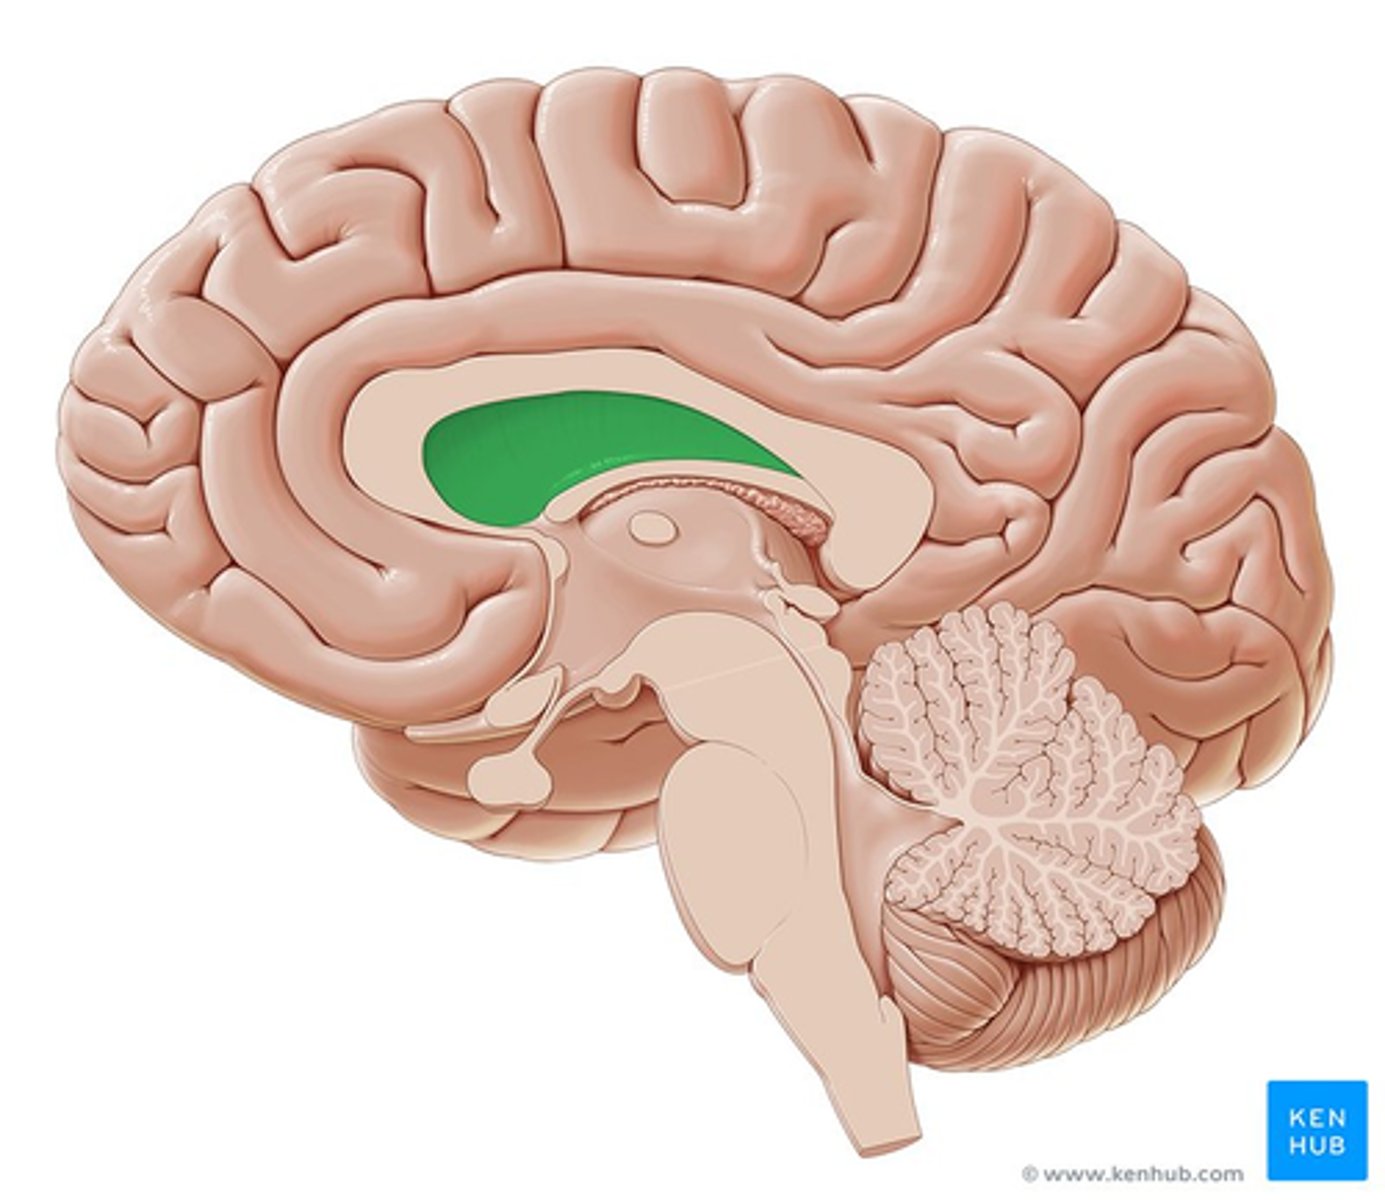

lateral ventricle